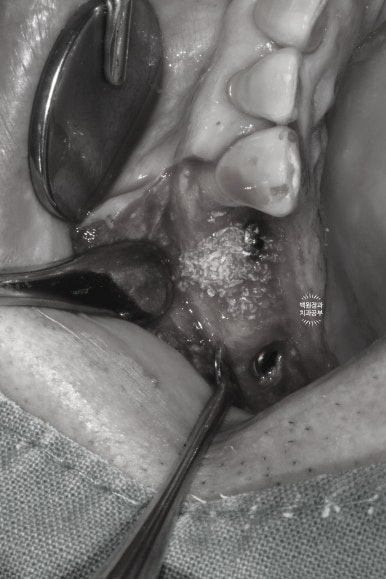

치주염으로 다수의 치아를 발치하셨던 환자분들은

기존의 만성치주염으로 인해 본인의 잇몸뼈를 많이 잃으셨던 분들이기에,

다수의 치아에 뼈이식이 필요하게 됩니다.

이로 인해 치조골 이식술 (골유도재생술) 부터 상악동 골이식술, 블록본 이식술 등 여러 수술 테크닉이 동반되게 되죠.

생각보다 엄청난 공이 들어가는 수술입니다 !! 전문가의 섬세한 손길이 필요한 :)

수술 하고 봉합 후 사진입니다!

으... 너무 아파보인다 ㅠㅠ 라고 많이들 생각하시지만,

실제로 마취를 넉넉히 하고 하기 때문에 하나도 아프지 않습니다........

보통 이를 빼는 것보다 임플란트 수술이 덜 아프다고들 하세요!